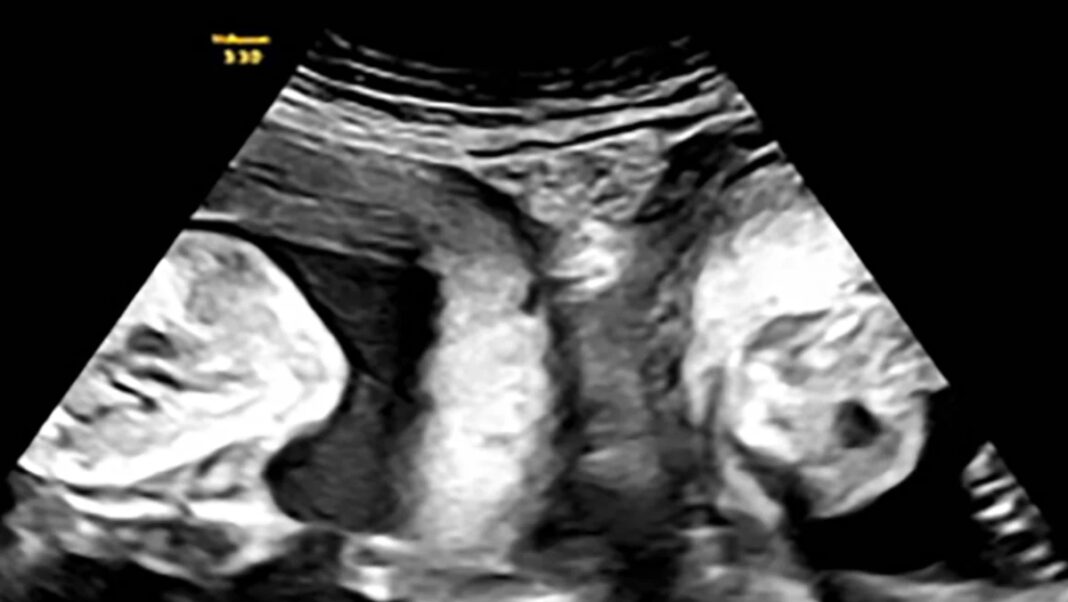

Μια γυναίκα με δύο μήτρες γέννησε δίδυμα, ένα από κάθε μήτρα, τον περασμένο μήνα σε νοσοκομείο της βορειοδυτικής Κίνας, σύμφωνα με αξιωματούχους του τομέα της υγείας και κρατικά μέσα ενημέρωσης. Η Li γέννησε ένα αγόρι και ένα κορίτσι με καισαρική τομή, όπως ανακοίνωσε το Λαϊκό Νοσοκομείο Xi’an στην επαρχία Shaanxi, κάνοντας λόγο για ένα περιστατικό που συμβαίνει «μια φορά στο εκατομμύριο».

«Είναι εξαιρετικά σπάνιο να συλληφθούν δίδυμα με φυσικό τρόπο σε κάθε κοιλότητα της μήτρας και ακόμη πιο σπάνιο να κυοφορηθούν μέχρι τέλους», ανέφερε το νοσοκομείο στον επίσημο λογαριασμό του στην κινεζική πλατφόρμα κοινωνικής δικτύωσης Weibo στις 18 Σεπτεμβρίου. Σύμφωνα με το νοσοκομείο, η νέα μητέρα γεννήθηκε με δύο τραχήλους και δύο μήτρες, μια κατάσταση που ονομάζεται δίδελφυς μήτρα και απαντάται σε περίπου 1 στις 2.000 γυναίκες.

Η ιστορία της έγινε viral στα κινεζικά μέσα κοινωνικής δικτύωσης, με περισσότερες από 50 εκατομμύρια προβολές τις τελευταίες ημέρες. Το νοσοκομείο αποκάλυψε επίσης ότι η νεαρή μητέρα είχε μείνει έγκυος άλλη μια φορά αλλά είχε αποβάλλει. Τον Ιανουάριο, όμως, η Li έμεινε ξανά έγκυος και ανακάλυψε κατά τη διάρκεια ενός υπερηχογραφήματος ότι κυοφορούσε δίδυμα – ένα σε κάθε μήτρα.

Μετά από «στενή και αυστηρή» ιατρική παρακολούθηση, η γυναίκα γέννησε με «επιτυχία» ένα αγόρι βάρους 3,7 κιλών και ένα κορίτσι βάρους 3,1 κιλών, σύμφωνα με το νοσοκομείο.